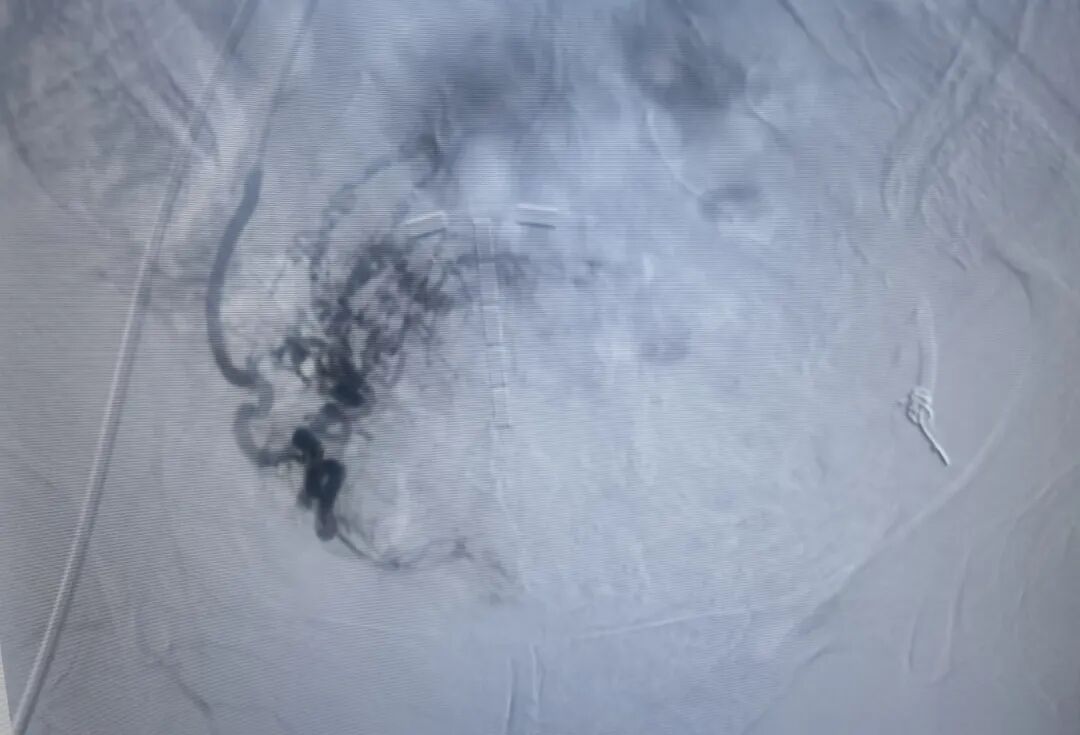

右侧子宫动脉栓塞术前